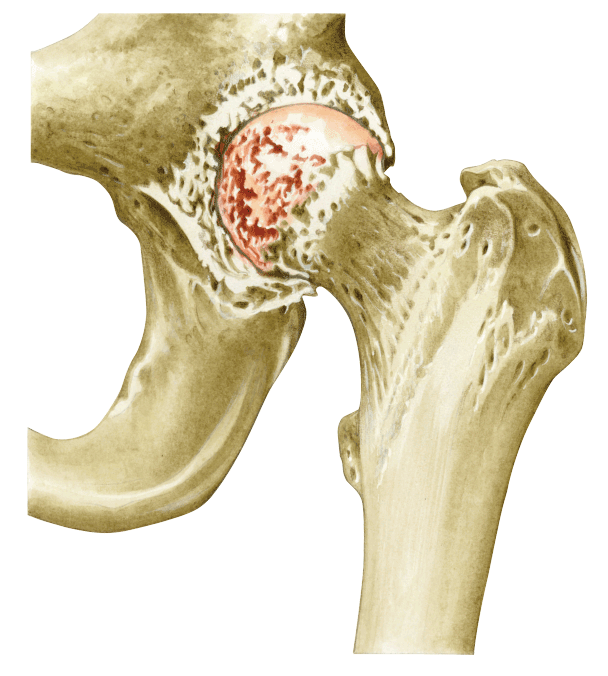

Dolor de cadera por artrosis:

Hacer reposo

Evitar la flexión repetida de la cadera y la presión directa sobre ella.

Evitar dormir sobre el lado afectado.

Evitar estar mucho tiempo sentado.

Aplicar hielo siempre sobre una toalla. Puede resultar útil un baño con agua tibia antes de iniciar ejercicios de estiramiento para reducir el dolor.

Ingerir los analgésicos indicados por el médico.